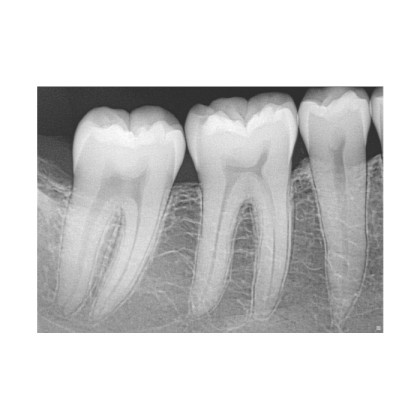

Главная особенность XIOS XG Supreme – это превосходное качество изображений, достигаемое за счет сочетания трех ключевых технологий:

⚙️ CMOS-APS (активный пиксельный сенсор) – современный метод формирования рентгеновских снимков, обеспечивающий высокую детализацию и низкий уровень шумов.

⚙️ CsI (йодид цезия) – специальный сцинтилляционный слой, который минимизирует рассеивание света и усиливает четкость изображения.

⚙️ Разрешение 33,3 пар линий/мм – одно из лучших в своем классе, что позволяет визуализировать мельчайшие анатомические структуры.

Уникальная функция, обеспечивающая автоматическое регулирование параметров снимка в зависимости от клинической ситуации. Прибор позволяет вручную или автоматически настраивать резкость, яркость и контрастность, выбирая один из четырех предустановленных режимов:

✔ Диагностика кариеса – высокая контрастность для лучшей визуализации поврежденных тканей. ✔ Эндодонтические исследования – детализация мельчайших каналов зубов. ✔ Ортодонтия – чёткое отображение костных структур и мягких тканей. ✔ Периодонтология – улучшенное воспроизведение состояния десен и пародонтальной ткани.